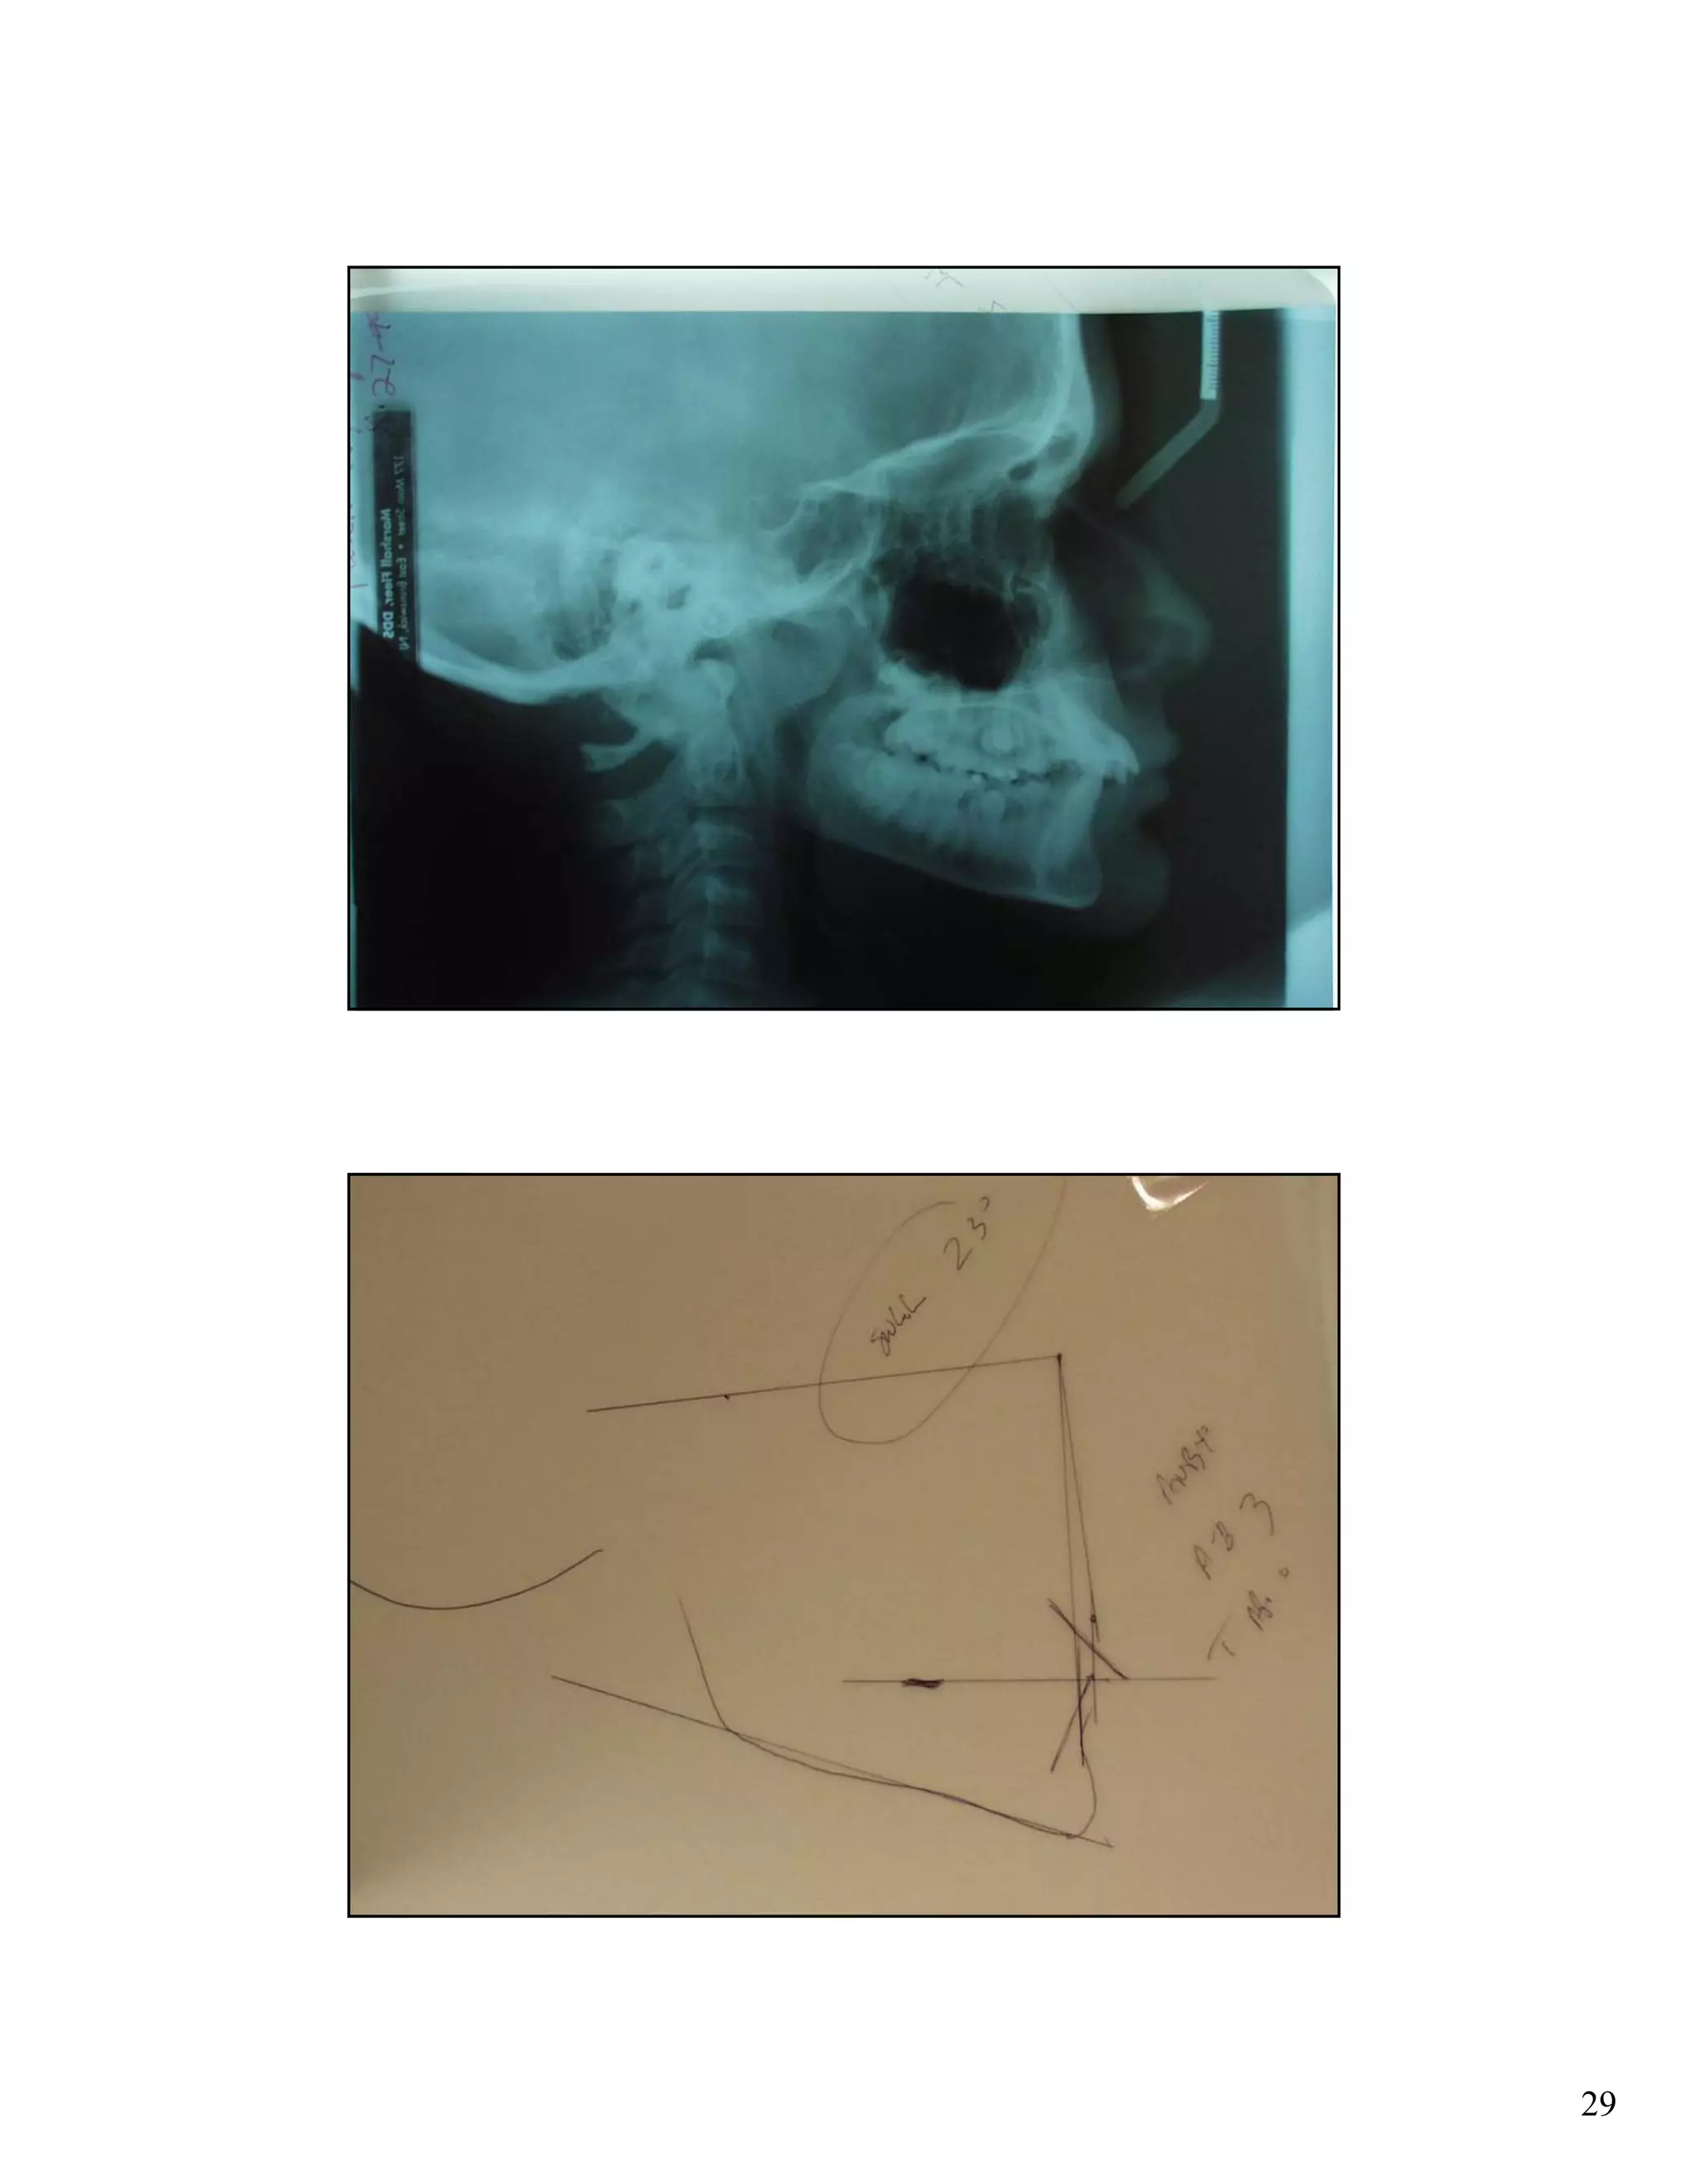

Cephalometric analysis uses x-rays of the skull to measure the growth and development of facial structures. Key indicators include the SN:GoGn angle measuring lower facial growth direction, the S-Go/N-Me ratio comparing posterior and anterior facial heights, and extension of the GoGn line to the occiput. These measurements help assess growth trends and plan orthodontic treatments.